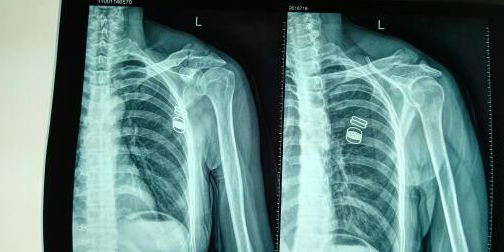

首先,患者接受了CT扫描,杭州博型科技利用这些数据进行三维重建,生成了患者肱骨的精确三维模型。这使得医生能够更清晰地了解骨折的具体情况,为手术制定了详细的预案。同时,杭州博型科技还利用3D打印技术制作了患者肱骨的实体模型,以便医生在手术前进行模拟手术。

在充分了解患者骨折情况和预演手术过程后,医生采用了个性化的矫形工具,进行了精确的手术治疗。术后患者的恢复进展顺利,手术效果显著。这一案例充分展示了杭州博型科技的3D打印和CT重建技术在肱骨大结节骨折治疗中的优势。